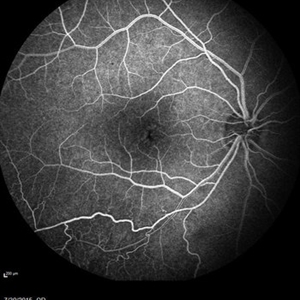

Retinal Dystrophy of 24-Year-Old Male Early FA OD

Nov 25 2015 by Zach Dupureur

Fluorescein angiography of a 24-year-old male. Juvenile retinoschisis on OCT. FA shows outer retinal staining. Could be associated with Goldmann Farve Syndrome.

Condition/keywords: Goldmann-Favre Syndrome, juvenile retinoschisis, retinal dystrophy